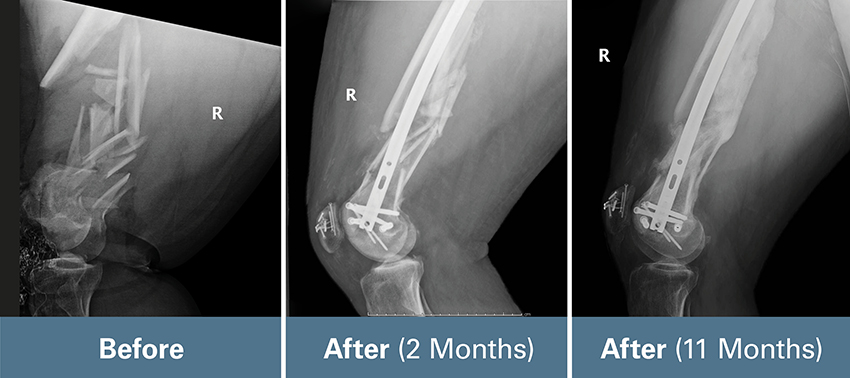

Tinubu assessed Johnny’s injuries: a severe open femur fracture and patella fracture, as well as injuries to his right upper extremity. Johnny needed surgery.

Johnny had five surgeries in one week. An early surgery involved adjusting pins on the external fixator that had been attached to the bone of his injured leg to keep the fractured bone stabilized, aligned, and the leg at the appropriate length. His open fracture, meaning the broken bone pierced his skin, required antibiotics to decrease the risk of infection. Tinubu later repaired the femur with a combination of screws and a rod. It was a challenging case.

“His joint surface was broken into many pieces, and it was difficult to reconstruct that, put it back together, and secure it in such a way that it doesn’t interfere with long-term function,” Tinubu said. “And then everything had to be properly aligned so his leg would be the same length, the appropriate rotation, and held in place until the body could heal.”

Tinubu accomplished everything he needed to get Johnny as close to 100% as possible. Given the severity of his original injury, Tinubu was happy with the results. Johnny walked with a mild limp at his one-year post-op appointment, but without any assistive devices.